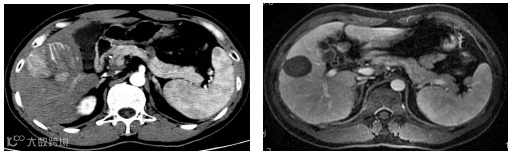

图1.病例54岁,肝右叶5.5×5.4cm肝癌(左图),行TACE+消融肿瘤完全坏死并缩小(右图),现患者已生存14年